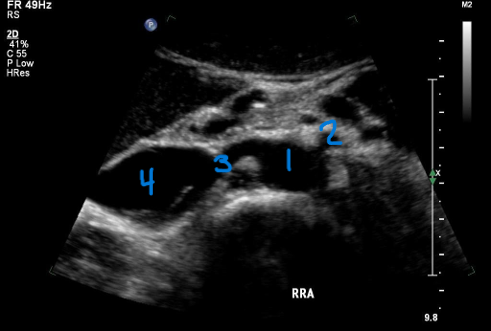

<p>In this transverse view, what is #1?</p>

In this transverse view, what is #1?

Aorta

<p>In this transverse view, what is #2?</p>

In this transverse view, what is #2?

Common Hepatic Artery

<p>In this transverse view, what is #3?</p>

In this transverse view, what is #3?

Left Splenic Artery

<p>What number is known as the RRA</p>

What number is known as the RRA

#3